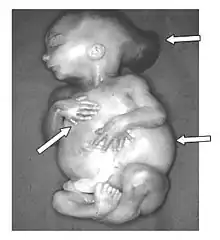

Enfin, il est le premier à distinguer un rapport unitaire dans un ensemble de malformations différentes, comme le syndrome de Meckel, dit aussi syndrome de Gruber, ou de Gruber-Meckel[5].

Les théories et interprétations de Meckel le Jeune, foncièrement vitalistes, sont devenues obsolètes[4], avec la mise en évidence à la fin du XIXe siècle, des mécanismes physico-chimiques du développement de l'embryon[8]. Toutefois, l'exactitude de ses descriptions est remarquable, par exemple la réalité et l'authentification du syndrome de Meckel a été établie en 1969[10].

La plupart de ses préparations tératologiques sont encore conservées en Allemagne, quelques-unes ont fait l'objet de nouvelles études génomiques en 2002[11].

- Beschreibung zweier durch sehr ähnliche Bildungsabweichungen entstellter Geschwister (syndrome de Meckel). Deutsches Archiv für Physiologie, 1822, 7: 99-172.